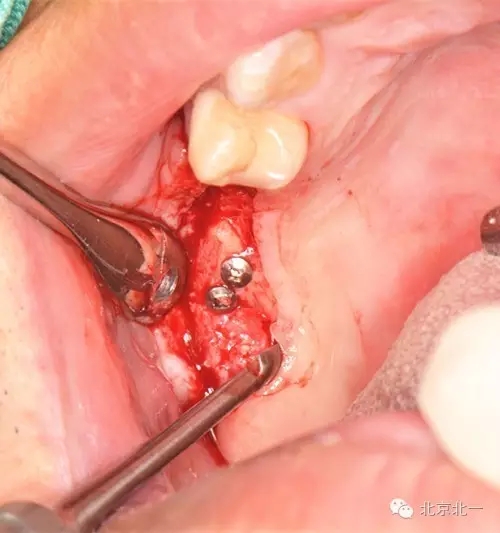

圖七:骨塊堅強內(nèi)固定

圖八:骨替代品協(xié)同使用。

圖九:蓋膜(可吸收bio-gide膜)蓋雙層膜